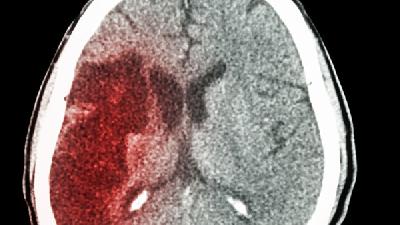

虽说很多的人都不希望看到自己的宝宝出现了脑瘫症状,但是很多的人还是想通过一些异常症状来判断孩子是否患上脑瘫,这时候了解脑瘫症状就非常重要了。脑瘫症状是什么样那么,脑瘫症状是什么样的呢?下面我们就一起来看一下专家的介绍。

脑瘫症状包括:

1、运动发育落后,不能达到上述相应月龄孩子具备的能力。

2、肌张力及姿势异常,如大腿外展困难、膝部屈曲不易伸直、竖立抱起时双腿伸直内收、两腿交叉呈剪刀状、上肢肘腕关节屈曲及手经常握拳而拇指内收。

3、主动运动少,5个月后仍不能主动伸手抓取自己喜欢的东西,或总用一只手去抓取。

4、出现异常反射,即一些原始反射延迟消失,而正常保护性反射减弱或不出现,还可能出现一些病理反射。脑瘫症状是什么样这是婴儿脑瘫的症状之一。

5、过度激惹:持续哭叫,入睡困难,大约有30%脑性瘫痪小儿在生后前3个月有类似严重“肠绞痛”的表现。